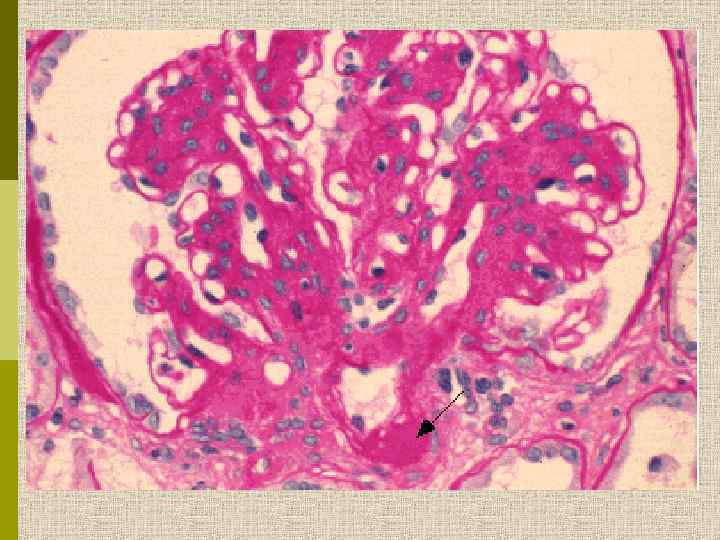

МОРФОЛОГИЧЕСКИЕ ИЗМЕНЕНИЯ ПРИ ДИАБЕТИЧЕСКОЙ НЕФРОПАТИИ Основные варианты - диабетический гломерулосклероз с узелками Kimmelstiel-Wilson - диффузный мезангиальный гломерулосклероз Характерные признаки Утолщение ГБМ; артериолярный гиалиноз; аневризматические капилляры; капсулярные капли; фибриновые шапочки; атрофия канальцев; инфильтрация, расширение и склероз интерстиция; линейные отложения иммуноглобулинов

PAS Узелковый гломерулосклероз (болезнь Киммельстиля-Вильсона) у больного с длительным течением сахарного диабета. Выраженное утолщением артериолы – типичный гилиновый артериолосклероз, наблюдаемый при сахарном диабете.